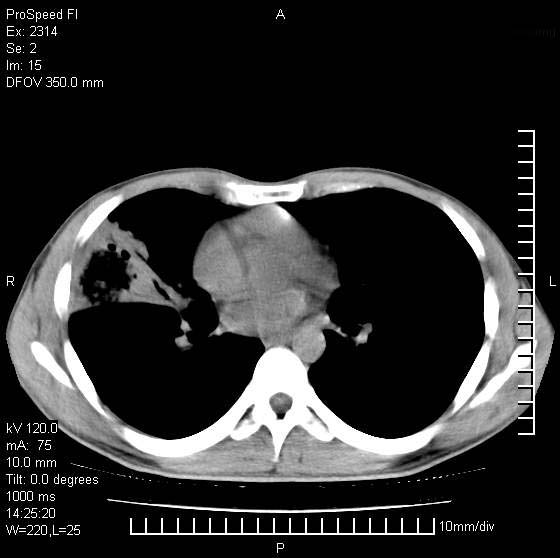

男性,再生障碍性贫血,入院前发热10天,最高40c,右侧胸痛,外院ct示右上,中肺边缘模糊的球性影(就是我现在图中标示的范围),考虑炎症,在我院使用头孢呋辛,洛美沙星10天,高烧消退,自感下午稍有发热,但今天ct示右上,中肺病灶明显扩大,还是考虑炎症,看其中的球型影是否霉菌感染??,是否能排除结核?

右肺中叶外侧段病变,上缘界限不清,下缘锐利,以段性发病为主,内见巨大空洞及空洞内容物,结合病史首先考虑:化脓性肺炎。不除外霉菌感染!

考虑霉菌感染.理由1\\有临床基础疾病,2\\有坏死的空腔,其内可见软组织影.

片状高密度影内见空洞影,内可见球形软组织密度影,并有新月征,考虑霉菌感染.